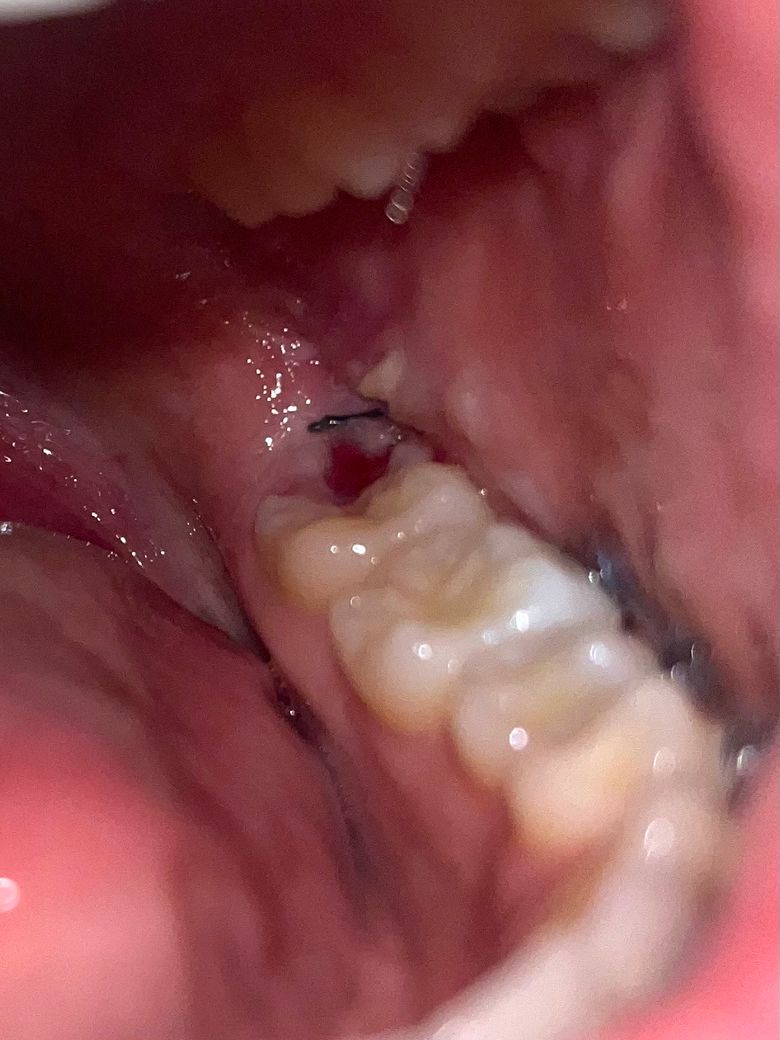

매복사랑니 발치 3일차 잘낫고있는건가요?

1.잘낫고있는거맞나요?

2.저 하얀부분은 왜저렇게되는걸까요?

낫는 과정인가요?

4.저 피가 혈병일까요?

• 1번 째 사진

특별히 염증이 있는 것은 아닌 것으로 보입니다. 미세한 출혈 등의 부작용은 곧 괜찮아질겁니다.

사진상으로 잘 아물고 잇는거 같습니다 아직은 피고 조금씩 나는거 같으니 자극이 가지 않도록 해주세요.

네 현재 잘아물고 있습니다.

치유과정중에 나타나는 증상입니다.

발치 후 초기에는 혈전이 형성되고, 이후 혈전이 치유된 조직으로 변하며 섬유조직이 생깁니다. 이 섬유조직이 하얗게 보일 수 있습니다. 이는 상처 치유의 정상적인 과정으로, 시간이 지나면서 점차적으로 사라집니다.

네 1-2주간 통증이 발생할수 있습니다.

네 혈병일 가능성이 높습니다.

서서히 좋아지나 1주일간은 통증이 나타날수 있으며, 만약 통증이 점점심해지거나 하는 경우에는 치과 진료를 받아보길 권합니다.